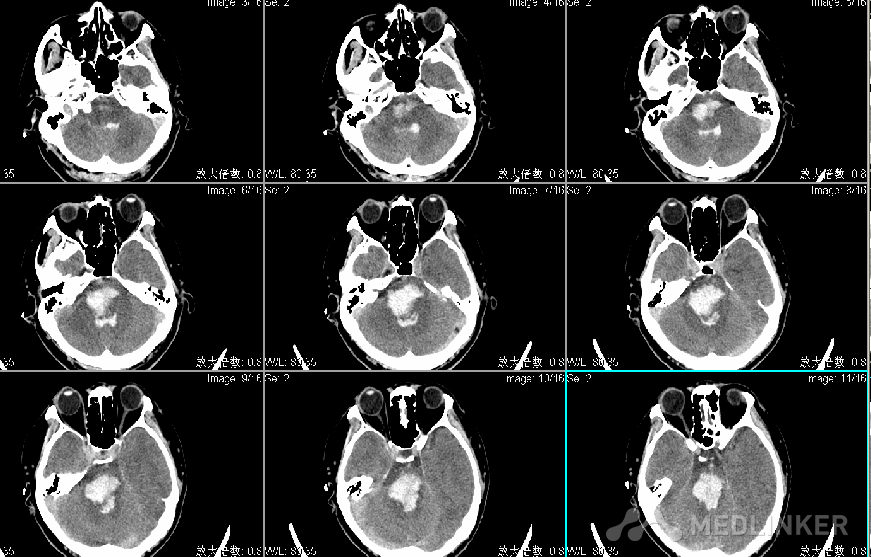

查体:T:36.3℃ P:73次/分R: 20次/分BP:154/107mmHg 嗜睡状态,呼之睁眼,应答切题,四肢可从嘱活动,GCS14分,双侧瞳孔直径左:右=2:2mm,光反射灵敏,可及水平眼震,额纹对称,颈软,左侧肢体4级,右侧肢体肌力5级,肌张力不高,腱反射(++),生理反射存在,双巴氏征(-)。入院头CT显示脑桥出血出血量约2ml。

入院诊断为:1.脑干出血 2.高血压病3级(极高危)3.吸入性肺炎。 入院后给予止血、控制血压及对症支持治疗,患者病情进行性加重,昏迷,四肢刺激强直,自主呼吸消失,复查头CT显示脑干出血多田公式计算约20ml,家属强烈要求手术治疗。